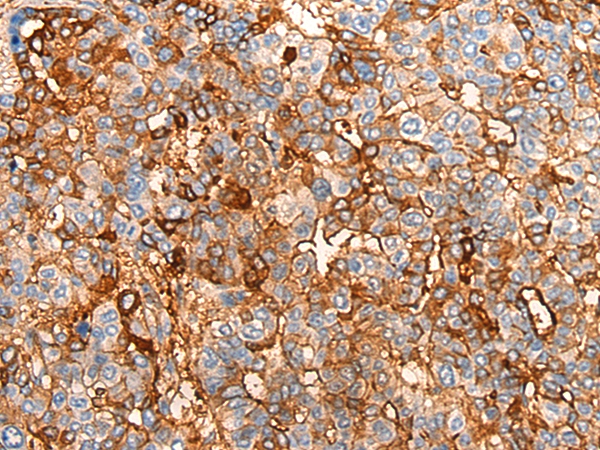

The image on the left is immunohistochemistry of paraffin-embedded Human liver cancer tissue using 46541(COX6A2 Antibody) at dilution 1/20, on the right is treated with synthetic peptide. (Original magnification: x200)